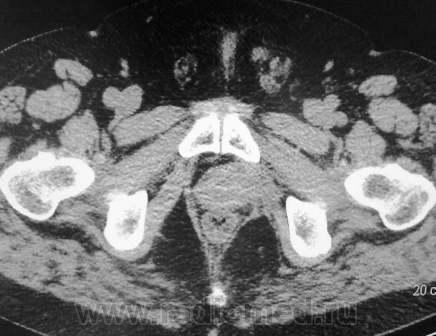

Множественные метастазы при раке простаты

После комбинированной терапии, динамики с сентября нет

Случай интересен, как по мне, в первую очередь локальностью да множественностью, ведь мы привыкли видеть т.н. "ватные" позвонки, кости таза да ребра....когда всего много...

Спустя 8 месяцев и еще 2 курса химиотерапии. И старые увеличились, и новые появились.